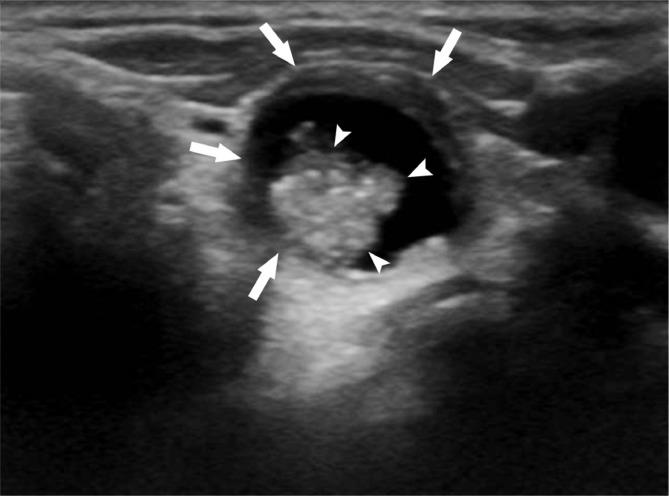

고형(solid): 초음파를 보면 액체 여부를 어느 정도 구별할 수 있는데 딱딱하게 보이는 구조물을 말합니다. 아래 사진은 알아보기 쉽게 액체와 고체부분이 섞여있는것을 가지고있는데요, 검은부분이 액체이고 그안에 밝은부분이 고체부분입니다.